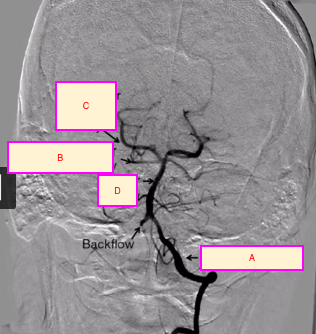

label A-D [4]

A: vertebral artery

B: superior cerebellar artery

C: posterior cerebral artery

D: basilar artery